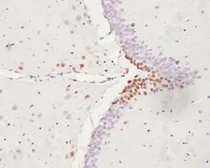

Product

Images